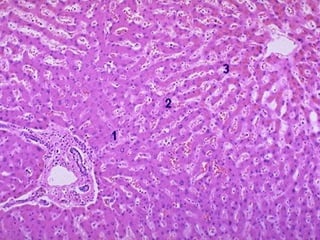

Nutmeg liver

Microscopically, the nutmeg pattern results from congestion

around the central veins, as seen here.

This is usually due to a "right sided" heart failure

.

• Liver is divided histologically into lobules.

• The center of the lobule is the central vein.

• At the periphery of the lobule are portal triads.

• Functionally, the liver can be divided into

three zones, based upon oxygen supply.

• Zone 1 encircles the portal tracts where the

oxygenated blood from hepatic arteries enters.

•

• Zone 3 is located around central veins, where

oxygenation is poor. Zone 2 is located in

between.